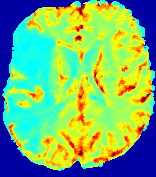

LesionRefer to captionRefer to captionRefer to captionRefer to captionRefer to captionRefer to caption𝐕rgbsubscript𝐕𝑟𝑔𝑏{\bf{V}}_{rgb}Refer to captionRefer to captionRefer to captionRefer to captionRefer to captionRefer to caption𝐕2subscriptnorm𝐕2{\|\bf{V}}\|_{2}Refer to captionRefer to captionRefer to captionRefer to captionRefer to captionRefer to captionRefer to caption3.53.53.52.82.82.82.12.12.11.41.41.40.70.70.70.00.00.0(mm/s)𝑚𝑚𝑠(mm/s)D𝐷DRefer to captionRefer to captionRefer to captionRefer to captionRefer to captionRefer to captionRefer to caption0.0200.0200.0200.0160.0160.0160.0120.0120.0120.0080.0080.0080.0040.0040.0040.0000.0000.000(mm2/s)𝑚superscript𝑚2𝑠(mm^{2}/s)Slice #1Slice #2Slice #3Slice #4Slice #5Slice #6

Figure 4: PIANO feature maps for another patient in the ISLES 2017 training set, where the lesion is located in the right hemisphere. Top row: segmented stroke lesion region (white) on different slices. The corresponding slices for the PIANO feature maps are shown in the following rows.

For a better insight into an estimated velocity field 𝐕𝐕{\bf{V}} and diffusion field 𝐃𝐃{\bf{D}}, we compute the following maps: (1) 𝐕rgbsubscript𝐕𝑟𝑔𝑏{\bf{V}}_{rgb}: Color-coded orientation map of 𝐕=(Vx,Vy,Vz)T𝐕superscriptsuperscript𝑉𝑥superscript𝑉𝑦superscript𝑉𝑧𝑇{\bf{V}}=(V^{x},V^{y},V^{z})^{T}, obtained by normalizing 𝐕𝐕{\bf{V}} to unit length and mapping its 3 components to red, green, blue respectively; (2) 𝐕2subscriptnorm𝐕2\|{\bf{V}}\|_{2}: 222 norm of 𝐕𝐕{\bf{V}}; (3) D𝐷D: scalar field in Eq. 5.

Fig. 3 and Fig. 4 show the PIANO feature maps estimated from two ISLES 2017 patients: all are highly consistent with the lesion in both cases. Details of the blood flow trajectories are revealed in 𝐕rgbsubscript𝐕𝑟𝑔𝑏{\bf{V}}_{rgb} by the ridged patterns and the sharp changes of colors in the unaffected (right) hemisphere, while the flat patterns appearing within the lesion provide little directional information about the velocity and indicate low velocity magnitudes. Velocity magnitudes are more directly visualized via 𝐕2subscriptnorm𝐕2\|{\bf{V}}\|_{2}, from which one can easily locate the lesion where 𝐕2subscriptnorm𝐕2\|{\bf{V}}\|_{2} is low. D𝐷D also indicates lower diffusion values in the lesion, though with less contrast potentially due to the fact that it captures the accumulated effect of CA diffusion at the voxel-level.